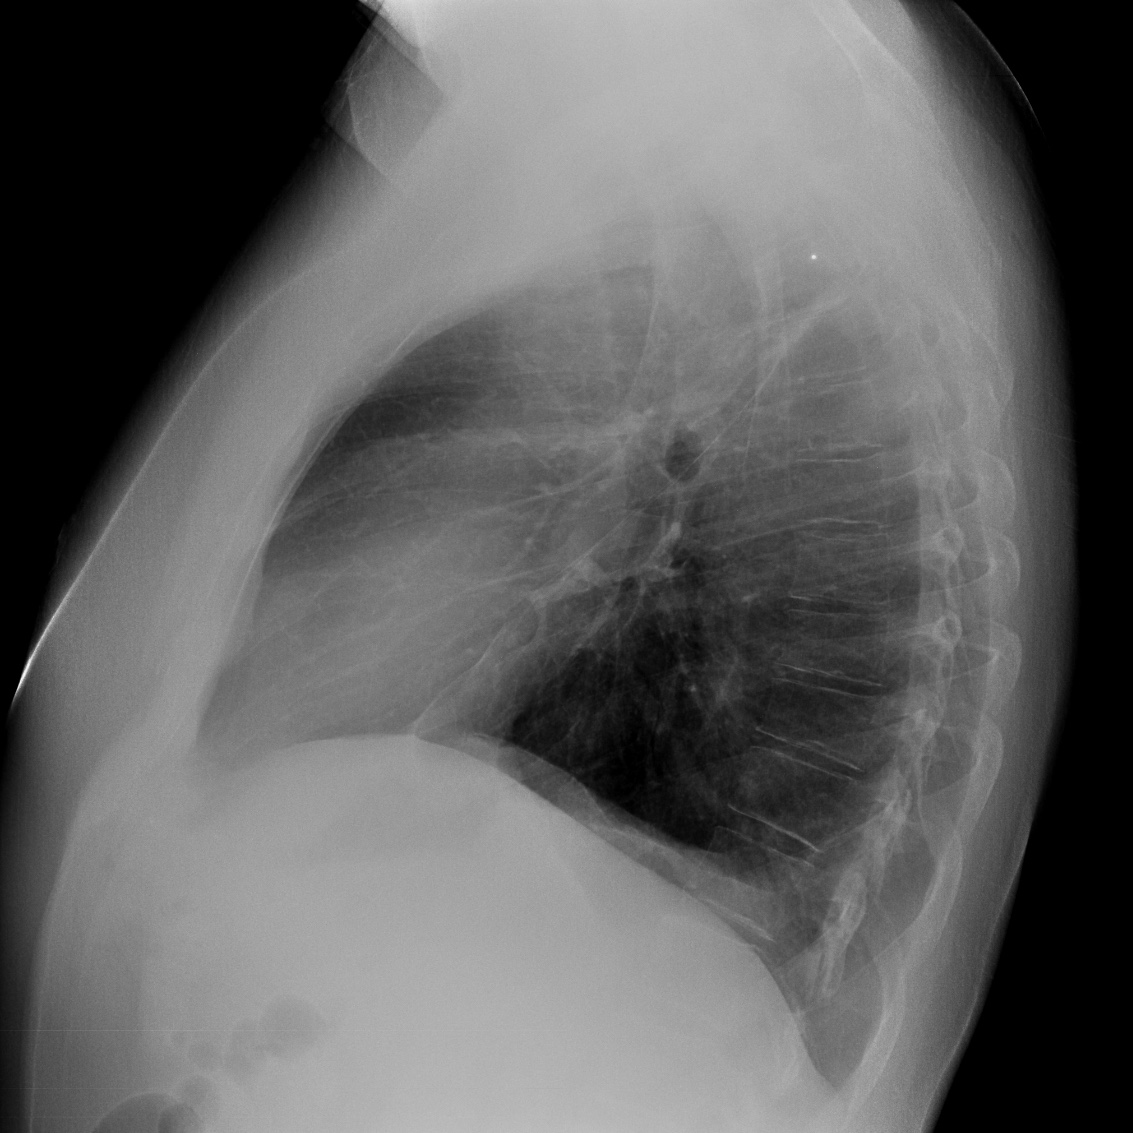

- Prótesis mamaria izquierda (obsevar el aumento de densidad homogéneo y de bordes bien definidos en la placa PA y lateral)

- Parénquimas pulmonares y silueta cardiomediastínica sin alteraciones significativas.